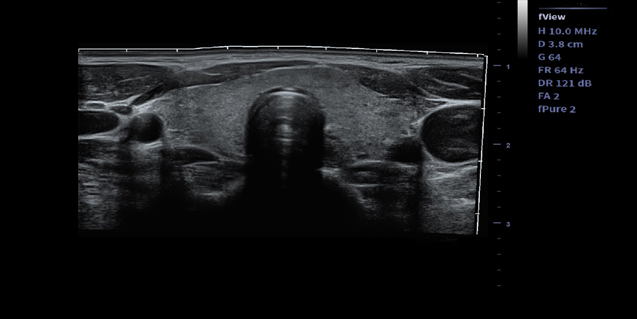

适用于浅表组织、小器官,神经,血管等